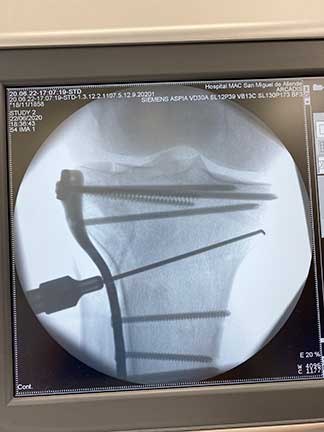

Fractura

de rodilla

Es la perdida de la continuidad del tejido óseo del fémur, tibia y rótula que integran la articulación de la rodilla, la cual dependiendo del número de huesos afectados, la cantidad de fragmentos y el desplazamiento nos orientan a un tratamiento y pronóstico.

¿Por qué se realiza?

El procedimiento es variable, puede ser quirúrgico o conservador dependiendo las características de la fractura y del paciente, el tratamiento que se debe realizar deberá ser planeado y personalizado a cada paciente englobado en colocación de fibras de vidrio, placas, tornillos, clavos o cerclajes.

Cuidados después de la intervención

Los tiempos de recuperación pueden variar dependiendo de la gravedad de la fractura y la estabilidad lograda con el tratamiento, el objetivo siempre será una rehabilitación acelerada para la reintegración del paciente a sus actividades cotidianas lo antes posible. El tiempo promedio es de 6 a 12 semanas.

Resultados esperados

El objetivo siempre será una reconstrucción anatómica, es decir, una reconstrucción lo más parecida a la anatómica normal previa a la fractura. Para lograr este objetivo es importante que el tratamiento sea realizado por médicos u ortopedistas expertos en fracturas articulares, lo cual mejoraría el resultado.